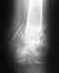

Re: Перелом голени со смещением отломков